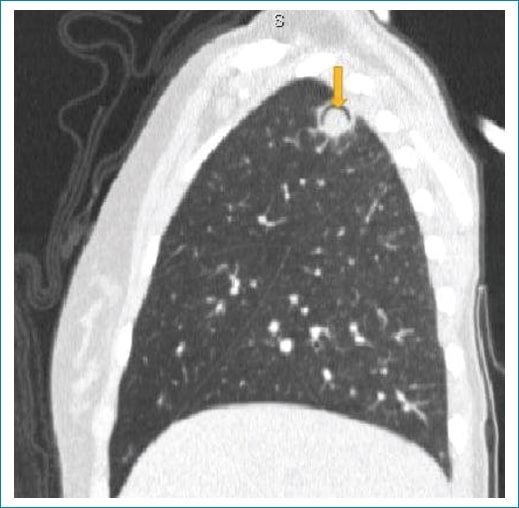

Figura 2. Tomografía computada con ventana pulmonar reconstrucción coronal. Se observa una cavidad redondeada en el lóbulo superior derecho apical, con un nódulo de tejido blando no dependiente; en su interior hay una sutil opacidad de vidrio esmerilado que rodea la lesión (flecha).

Aspergillus es un hongo filamentoso conformado por cadenas celulares llamadas hifas. Fisiopatológicamente, estas alteran las paredes de los vasos sanguíneos a través de las arterias bronquiales generando oclusión de la luz vascular, lo que lleva a la necrosis y cavitación. Esto se refleja radiológicamente como un área de vidrio esmerilado, consolidación y/o nódulos peribronquiales. En su evolución el centro infartado se retrae y se reabsorbe, resultado de la reacción neutrofílica, dejando un área de tejido desvitalizado que se desprende del resto de la consolidación2. El aire que se encuentra entre el tejido desvitalizado y el parénquima consolidado que lo rodea tiene forma de media luna o del aire creciente (Fig. 2). Este signo es tardío, coincide con una recuperación progresiva de la infección y depende de la función leucocitaria, por lo cual generalmente se observa en pacientes inmunocomprometidos, que en general inician clínicamente con cuadro de hemoptisis3.

Su diagnóstico es radiológico. Se observa en el 50% de los pacientes con aspergilosis. Otras de las causas menos frecuentes son tuberculosis pulmonar, aneurisma de Rasmussen, absceso pulmonar, cáncer de pulmón, hematoma pulmonar y neumonía por Pneumocystis4. Como diagnóstico diferencial podemos mencionar el signo de Monod, que consiste en la presencia de aire alrededor de una masa dentro de una cavidad pulmonar preexistente; pero este se presenta en paciente inmunocompetentes5.